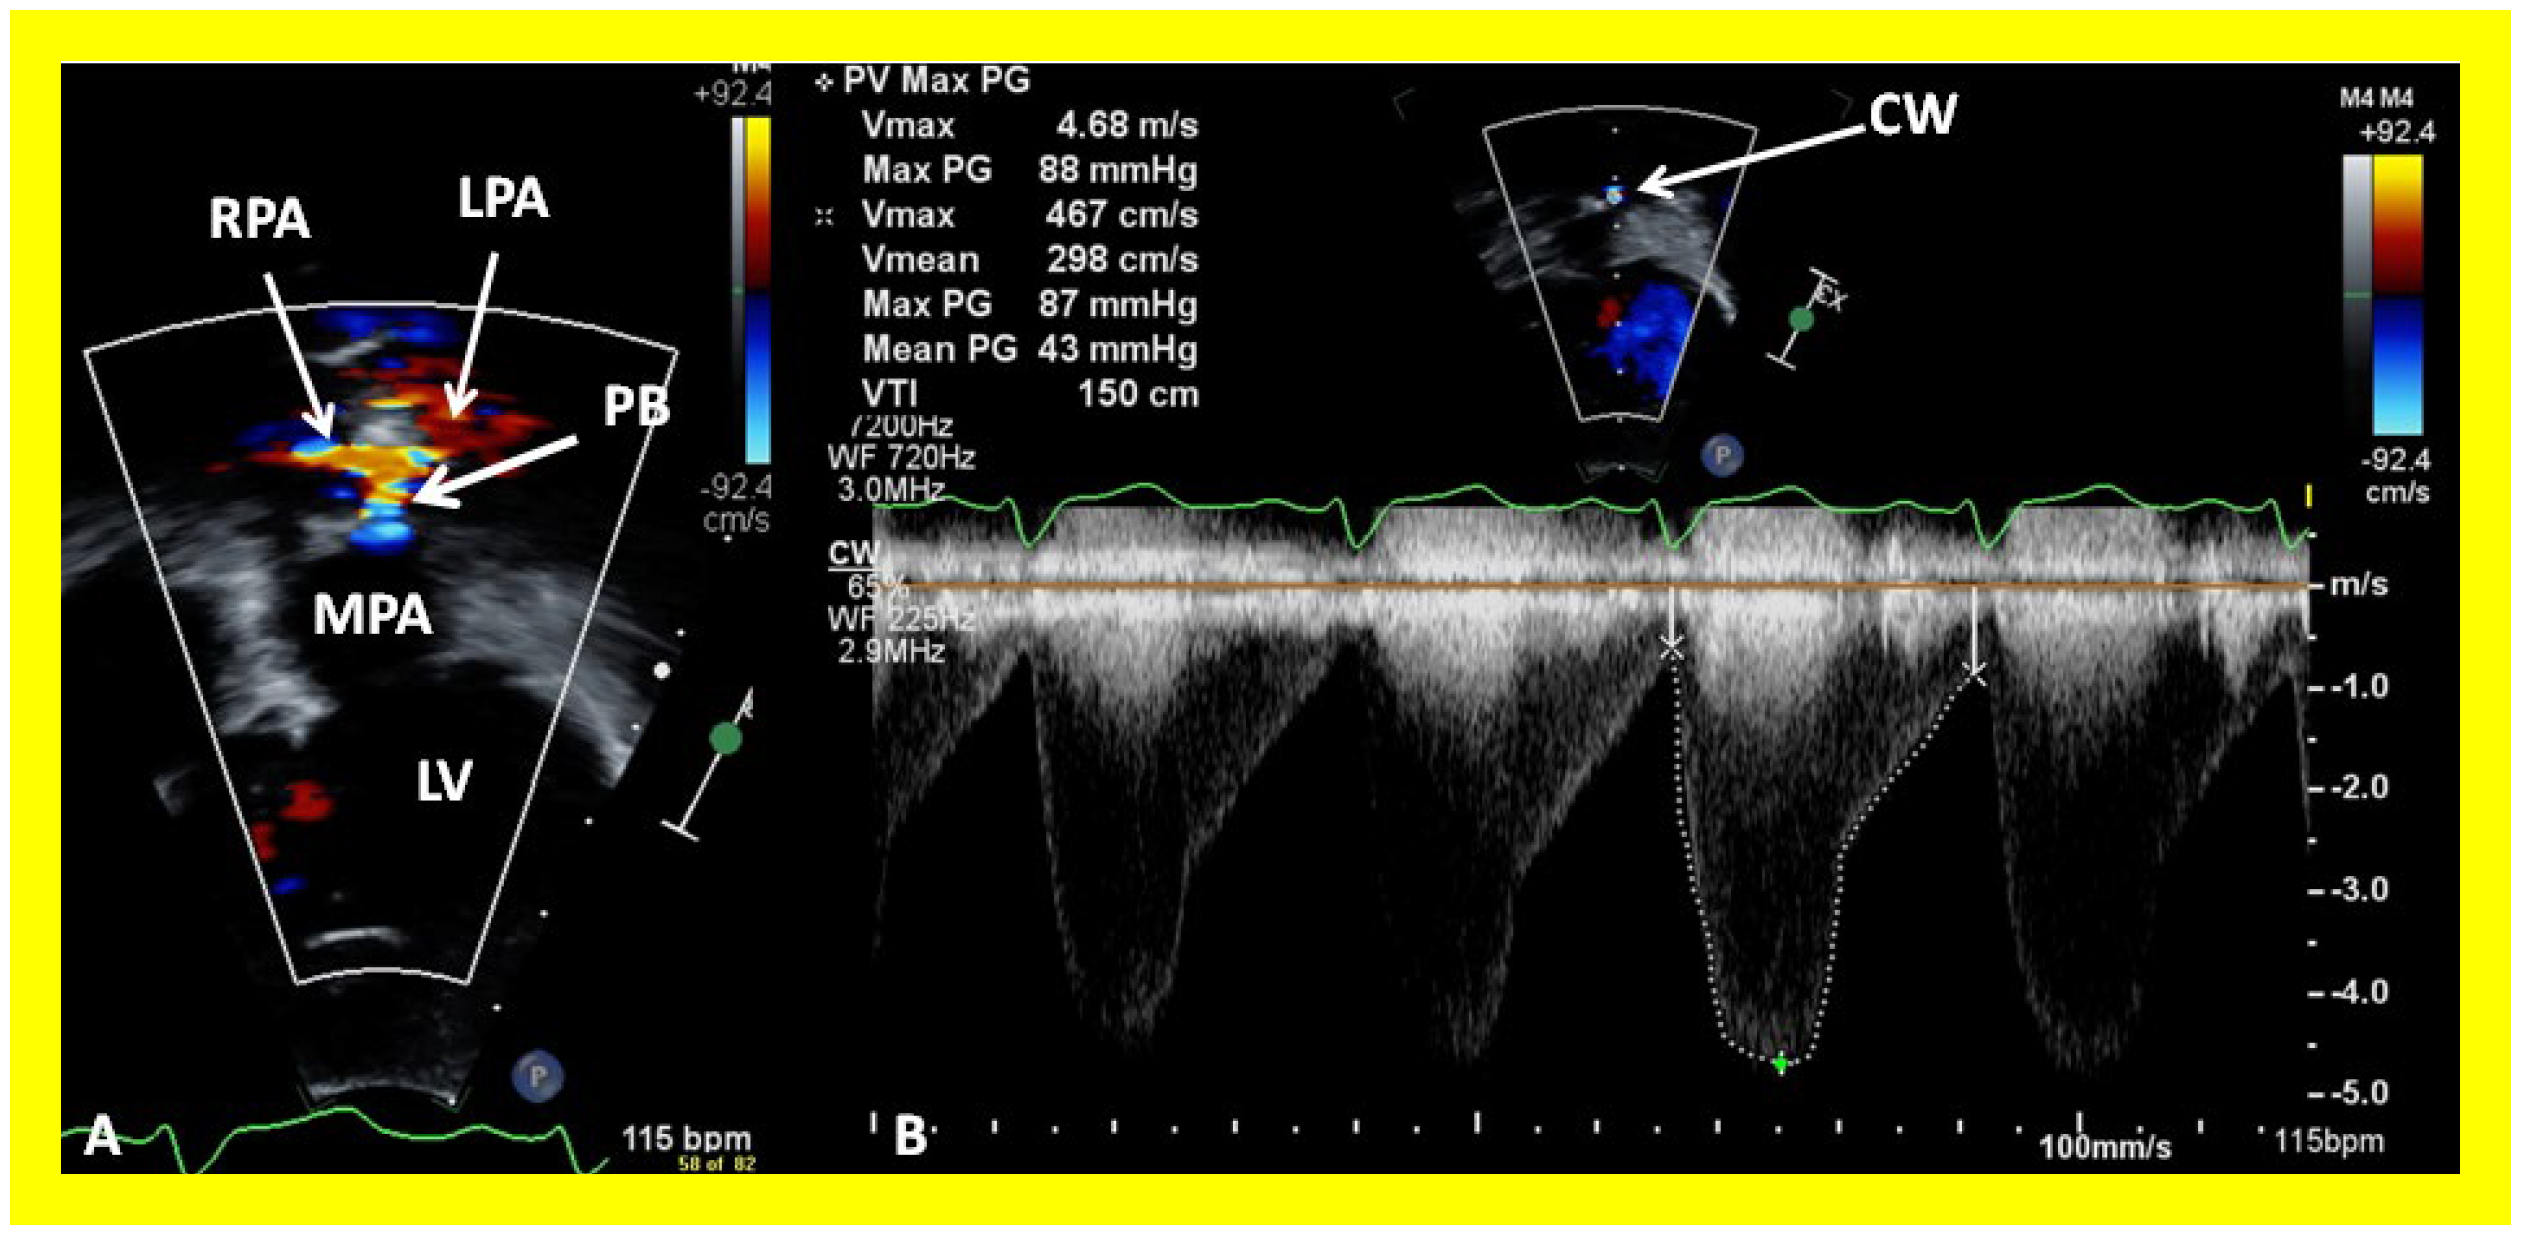

In patients who had banding of the PA, echo-Doppler studies should be scrutinized to demonstrate the banded PA diameter (Figure 22A,B and Figure 23A) and peak Doppler flow velocity across the banded PA (Figure 22C and Figure 23B); high Doppler velocity across the band (Figure 22C and Figure 23B) would suggest effective palliation. Low gradients and ineffective control of CHF may require tightening of the band; echo-Doppler evaluation is useful in making such an assessment.

Figure 23. Selected echocardiographic video frames demonstrating pulmonary artery band (PAB) with narrow diameter by color flow (A) and a high gradient (88 mmHg) by continuous wave Doppler (B) are shown.

Applsci 11 09472 g023